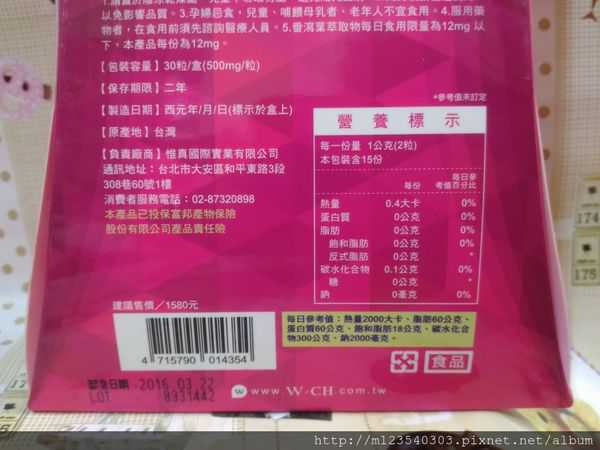

每一盒Supercut塑魔纖立塑膠囊都有三小包,每一小包有10顆膠囊

Supercut塑魔纖立塑膠囊的成分有:瓜拿那萃取粉、肉桂萃取粉、辣椒萃取物(唐辛子)、吡啶甲酸鉻、番瀉葉粉末、玉米澱粉、氧化鎂、二氧化矽。

食用方式:早晚餐前30分鐘各1粒,每日不超過2粒。(多食無益)

番瀉葉萃取物每日食用限量為12mg以下,

番瀉葉萃取物每日食用限量為12mg以下,